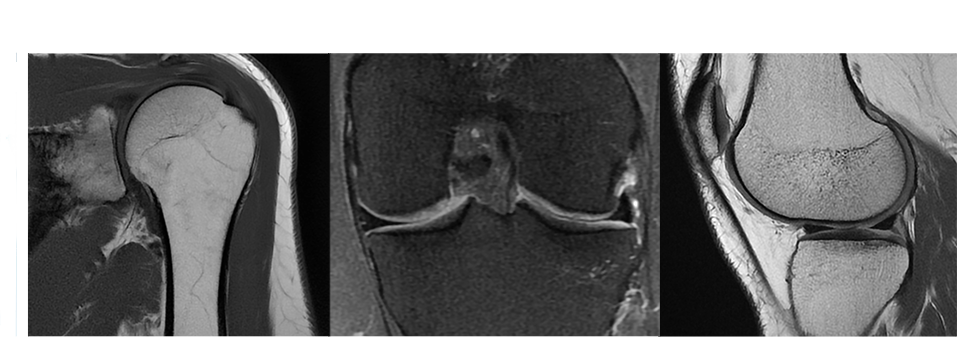

OrthoWorksは整形領域でご活用頂ける最新のソフトウェアアプリケーション群です。

MAVRIC SLは整形領域のMRI対応インプラントによる金属アーチファクトを抑制するアプリケーションです。マルチスペクトラルRFと3D VAT法を組み合わせて3次元で歪みを低減します。

PROPELLER MBは体動補正アプリケーションPROPELLERにマルチショットブレード法を用いることで、T1強調画像などより多くのコントラストに対応しました。PaedWorks